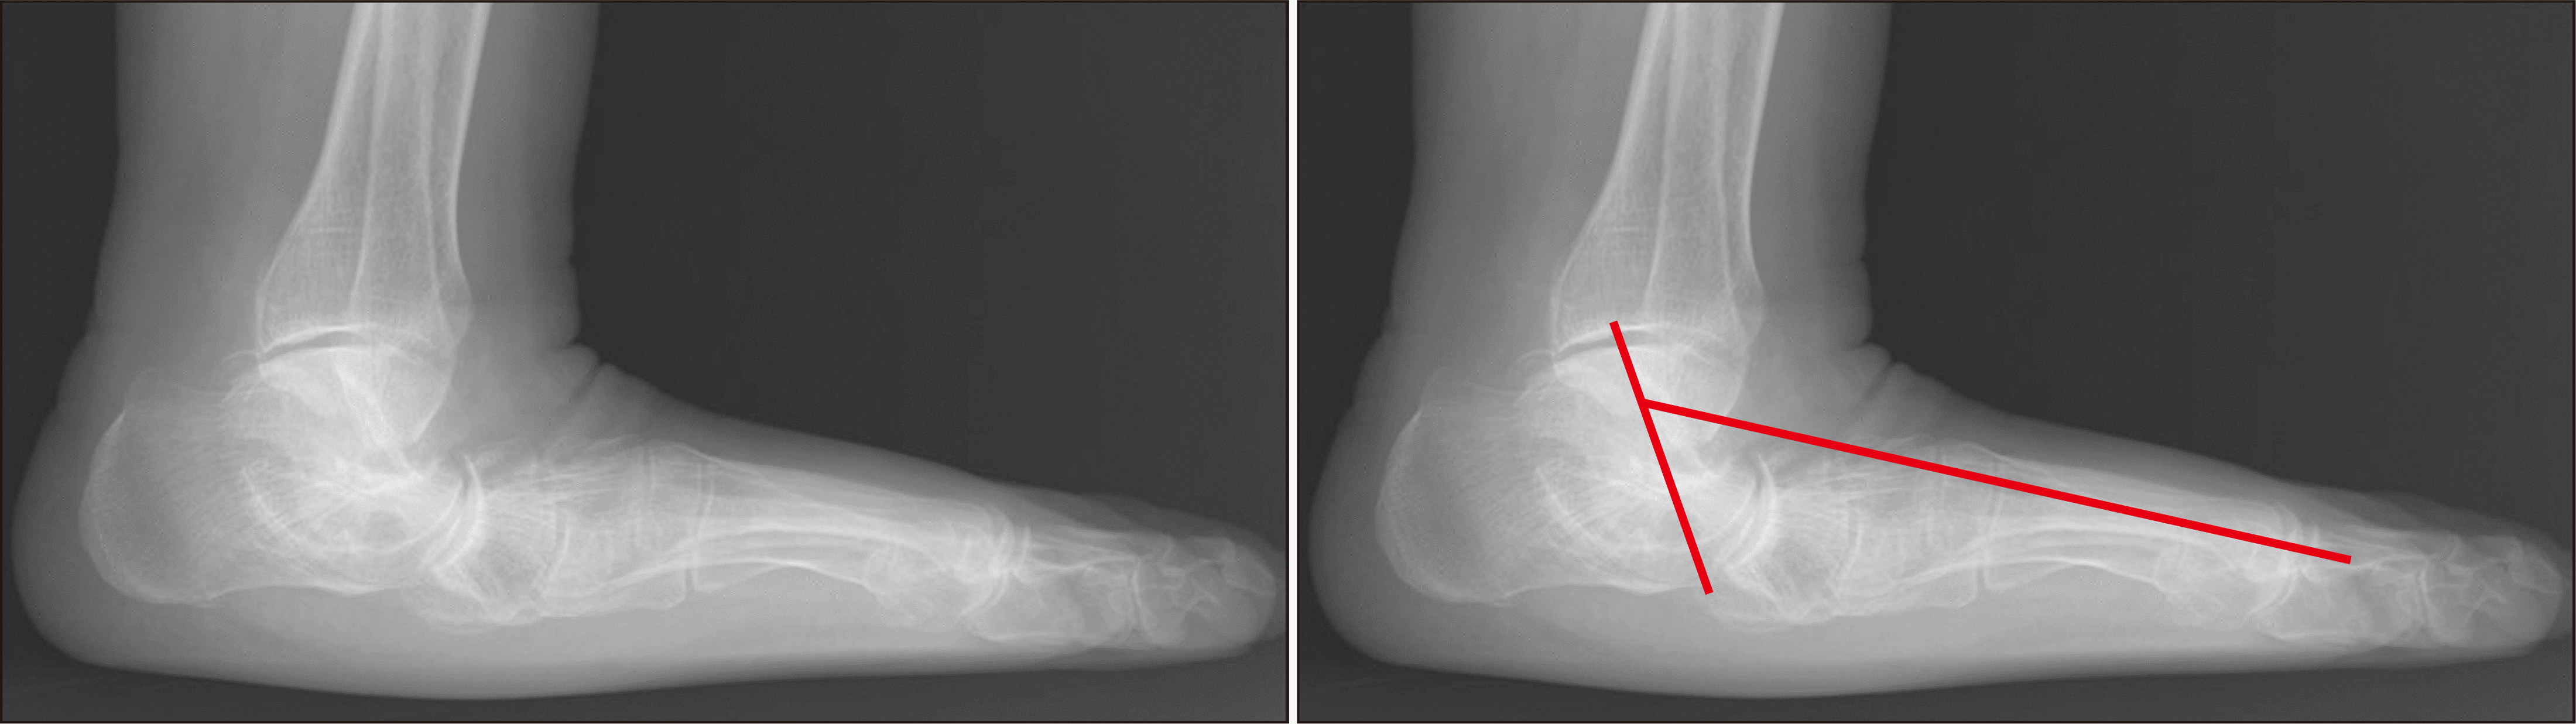

체중부하 방사선 촬영은 편평족의 진단에 있어 가장 표준이 되는 검사로, 체중부하 족부 전후면, 족부 측면, 족관절의 전후면 혹은 모티스 영상(mortise view) 및 후족부 정렬 촬영(hindfoot alignment view)8) 등이 진단을 위해 권고된다.9) 족부 전후면 사진에서는 전족부 혹은 중족부의 외전 정도를 평가할 수 있으며 거주상 관절 피복각(talonavicular coverage angle), 거주상 관절 이탈률(talonavicular uncoverage percent) 등 이를 반영하는 매우 다양한 지표를 측정할 수 있다(Fig. 1). 족부 측면 사진에서는 내측 세로궁의 소실 정도를 평가할 수 있는데, 흔히 쓰이는 지표로는 Meary angle이라 불리는 외측 거골-제 1중족골 각도를 측정할 수 있다(Fig. 2). 또한 족부의 내측주(medial column) 관절들의 족저부 벌어짐(plantar gapping) 정도를 확인하여 내측주 불안정성 정도를 평가할 수 있으며 족근동에서 거골과 종골의 직접적인 충돌 혹은 족근동 주변 골의 경화소견이나 낭종성 병변 등을 통해 족근동 충돌을 간접적으로 확인할 수 있다(Fig. 3). 족관절의 전후방 혹은 모티스 사진에서는 거골의 외반경사(valgus talar tilt)의 유무를 통해 족관절의 불안정성을 평가할 수 있으며 변형이 많이 진행한 경우 비골하 충돌 또한 확인할 수 있다(Fig. 4). 마지막으로, 후족부 정렬 촬영을 통해서는 후족부 외반 변형의 정도를 평가할 수 있는데, 주로 후족부 정렬각(hindfoot alignment angle) 혹은 후족부 모멘트암(hindfoot moment arm)을 측정한다(Fig. 5).10)

새로운 분류체계는 변형의 종류와 위치에 따라 A~E로 나누고, 각 변형의 유연성 유무에 따라 1기 유연성 변형과 2기 강직성 변형으로 분류하였다(Table 2).6) 이러한 변형은 진찰 소견과 체중부하 단순 방사선 촬영을 통해 평가하도록 하였고, 체중부하 전산화 단층촬영의 경우 아직 전세계적으로 사용되고 있지는 않기 때문에 판단기준에서 제외되었다. A형 변형은 후족부 외반 변형으로 후족부가 신체의 정중선으로부터 외측으로 전위된 변형을 뜻한다. 임상적으로 진찰 시 후족부 외반이 관찰되거나, 후족부 정렬 영상에서 후족부 정렬각 혹은 후족부 모멘트암의 증가 등으로 판단할 수 있다(Fig. 5). B형 변형은 전족부 혹은 중족부의 외전 변형으로 전족부나 중족부가 후족부를 기준으로 외측으로 전위된 변형이다. 체중부하 족부 전후면 사진상 거골두에 대한 주상골의 피복(coverage) 정도가 감소하고, 거주상 관절 피복각이 증가한다(Fig. 1). 또한 이 변형에 의해 족근동 충돌이 발생할 수 있으며, 족근동 주변의 압통 및 통증이 발생할 수 있다. 체중부하 족부 측면사진상 족근동에서 거골과 종골의 직접적인 충돌 소견이 보이거나, 족근동 주변의 거골과 종골의 골경화 혹은 골낭종 등을 통해 간접적으로 확인할 수 있다(Fig. 3). C형 변형은 전족부의 내반 변형 혹은 내측주 불안정성으로 임상적으로 후족부를 중립 위치에 고정한 뒤 관찰하였을 때 전족부가 내반을 보이는 변형이다(Fig. 8). 일부에서는 이를 회외 변형으로 불러야 한다는 의견도 있으나 현재 혼용해서 쓰이고 있다.11,20) 내측주 불안정성은 체중부하 족부 측면사진상 거주상 관절, 주상설상 관절(naviculocuneiform joint) 및 족근중족 관절(tarsometatarsal joint)이 배측 불안정증을 보이는 것으로, 영상검사상 족저부 벌어짐 유무 등을 통해 내측주 불안정성의 유무 및 위치를 확인할 수 있다(Fig. 3). D형 변형은 거근관절의 탈구 혹은 아탈구 변형으로 거골이 종골을 기준으로 내회전, 족저굴곡되면서 종골은 거골을 기준으로 외회전, 외반, 외측 전위가 발생하면서 거골하 관절의 아탈구가 발생하고, 심한 경우 비골하 충돌을 일으키게 된다(Fig. 4). E형 변형은 발목관절의 외반 변형이 발생한 경우이며, 족관절의 전후방 혹은 모티스 사진에서 거골의 외반경사로 확인할 수 있다(Fig. 4). 이 분류의 적용은 한 환자에 대해 A 부터 E까지의 변형 유무를 확인하고, 각각의 변형이 유연성 변형인지, 강직성 변형인지에 따라 1기와 2기를 나누는 방식으로 적용한다.

Figure 3

Weight bearing foot lateral radiograph showing plantar gapping of naviculocuneiform joint (*) and tarsometatarsal joint (**). Sinus tarsi impingement (black arrow) and bony sclerosis around sinus tarsi (white arrow).